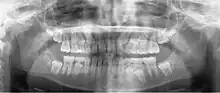

![]() A dental panoramic radiograph, showing the maxilla and mandible, all the teeth including the "wisdom teeth," the frontal and maxillary sinuses, the nasal cavity and the temporomandibular joint and other near by head and neck anatomy. | |

A panoramic radiograph is a panoramic scanning dental X-ray of the upper and lower jaw. It shows a two-dimensional view of a half-circle from ear to ear. Panoramic radiography is a form of focal plane tomography; thus, images of multiple planes are taken to make up the composite panoramic image, where the maxilla and mandible are in the focal trough and the structures that are superficial and deep to the trough are blurred.